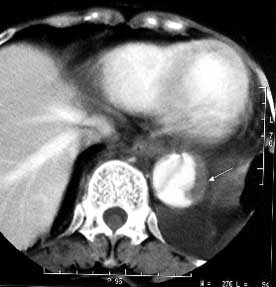

女性,71岁,胸骨后疼痛两小时来诊。体检:心界左下扩大,心率70次/每分,律齐,无杂音。x线胸片示:纵隔增宽。

ct平扫:降主动脉全程约18cm范围内管腔扩张,管腔被条索影分隔成前内、外后两腔,条索影与管壁连接处见散在点状钙化影。

增强扫描:见前内腔较小,与主动脉弓同步强化;后外腔较大,造影剂消退时间教主动脉弓延长,切管壁不均匀增厚,强化不明显。

ct诊断:降主动脉夹层动脉瘤,伴附壁血栓形成。